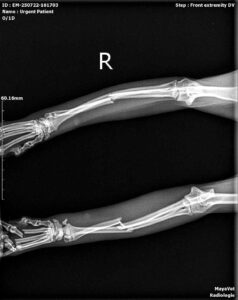

Din păcate, radiografiile au confirmat ceea ce bănuiam: ambele membre anterioare fracturate la nivelul radiusului si al ultei , iar Misha are nevoie de o intervenție chirurgicală ortopedică pentru a putea merge din nou și, mai ales, pentru a trăi fără durere.